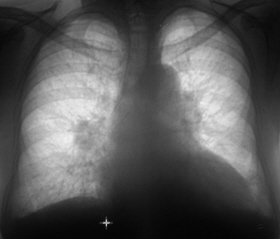

Иллюстрация 1. Флюорограмма. С обеих сторон определяется усиление и обогащение легочного рисунка. Тень правого корня локально в области тела расширена, частично гомогенизирована. Имеет место гипертрофия левого желудочка.